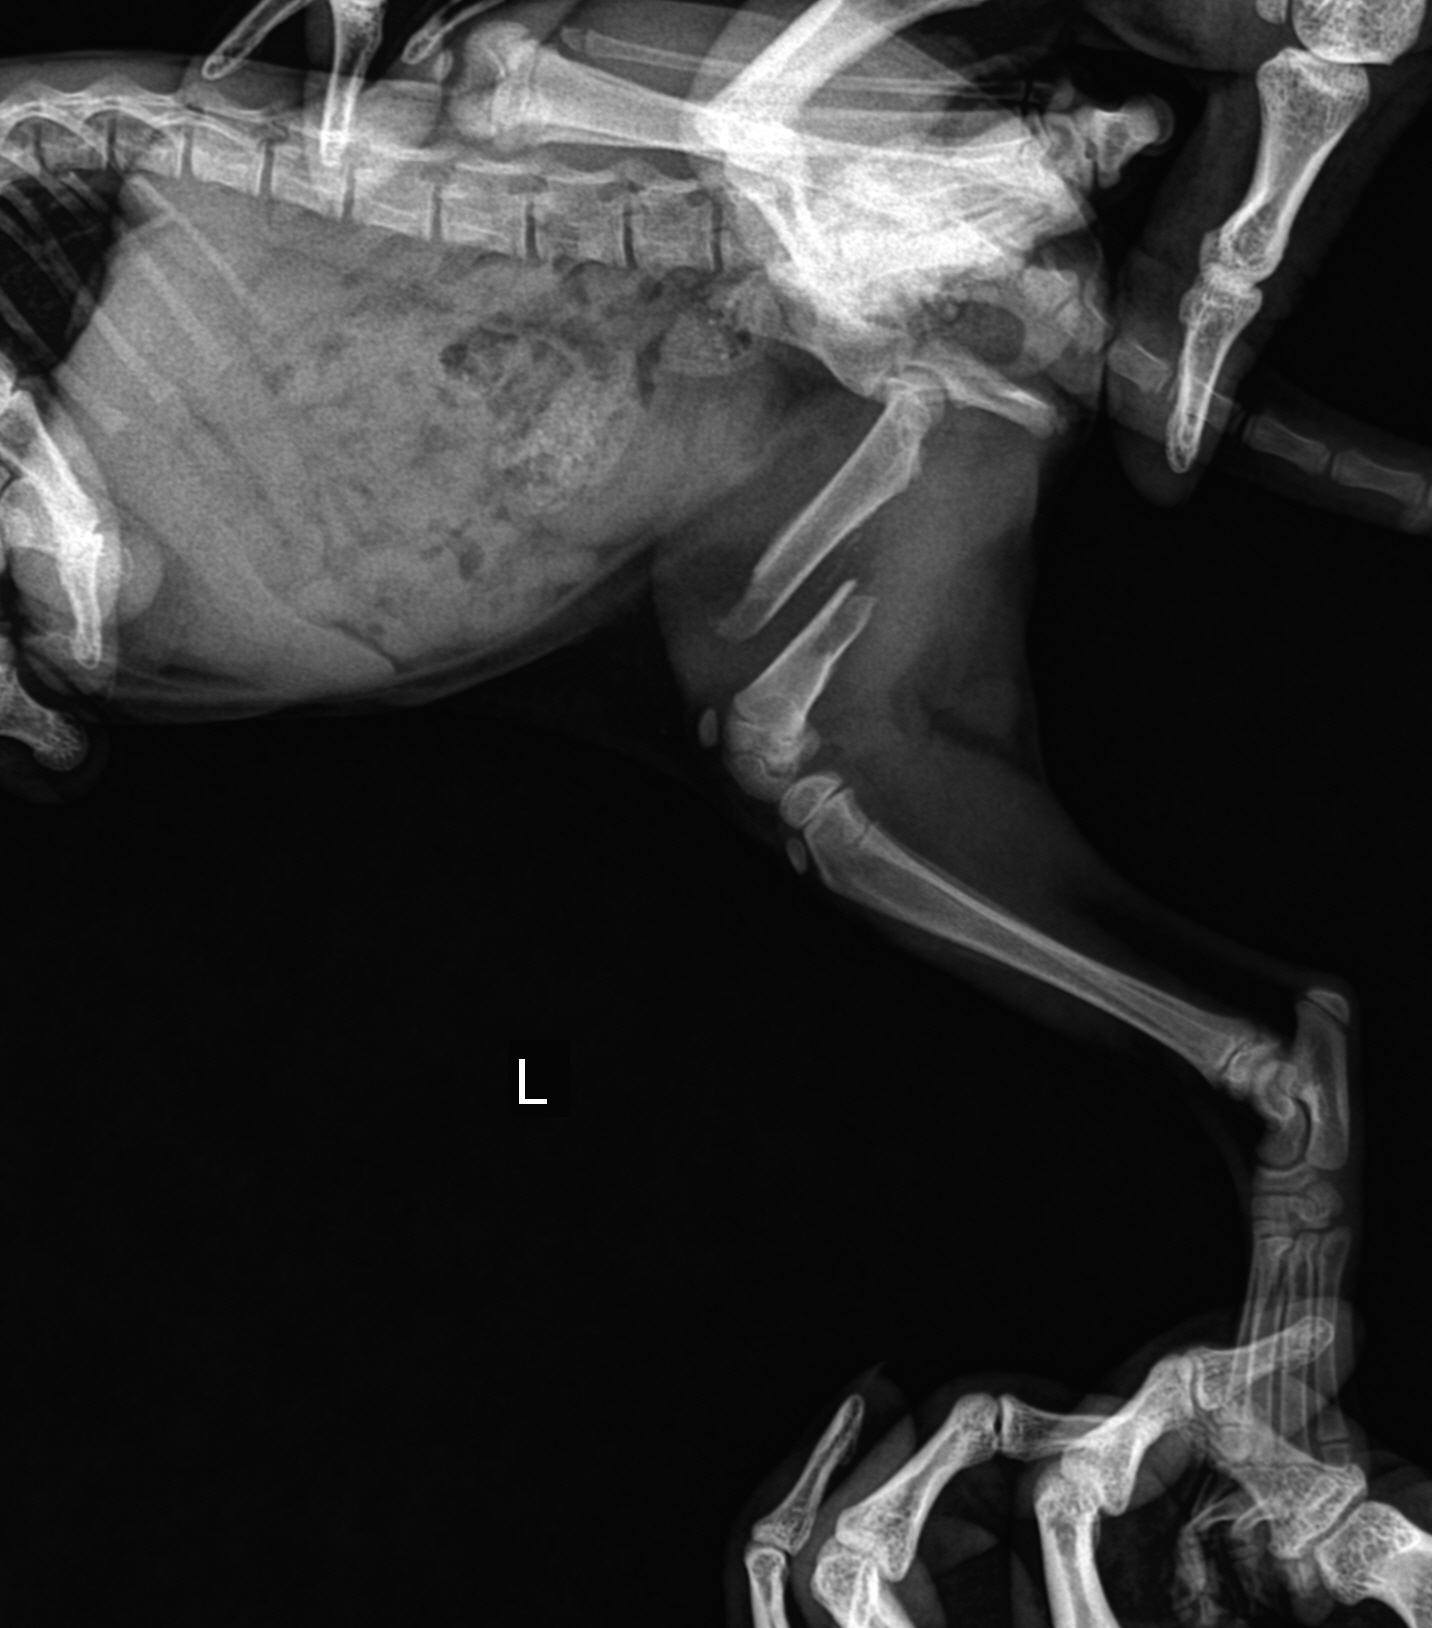

"왼쪽 뒷다리가 부러졌네요"

당장 엑스레이도 찍었다.

골절이었다.

그런데 너무 아기라 방법이 없다고 했다

그냥 저절로 붙기를 바라는 수 밖에.

어제 찍은 엑스레이 사진을 메일로 받아

원래 다니는 동물병원의 원장선생님께 보여드렸다.

선생님께서는 두가지 방법을 말씀해주셨다.

다리 근육을 잡아 당겨 뼈를 맞춘 후

핀을 박아 고정한다.

절개해서 뼈를 완벽하게 맞춘 후 봉합한다.

하지만 아이의 몸무게는 겨우 910g

1kg도 안되는 아이를 전신마취를 해서 수술을 시키는건

목숨을 걸어야하는 대 수술이었다.

선생님께서는 두가지 방법은 있지만 어렵다고 하셨고,

생각보다 아기 고양이의 뼈는 잘 붙는다고

이대로 두고 상황을 좀 지켜보자고 하셨다.